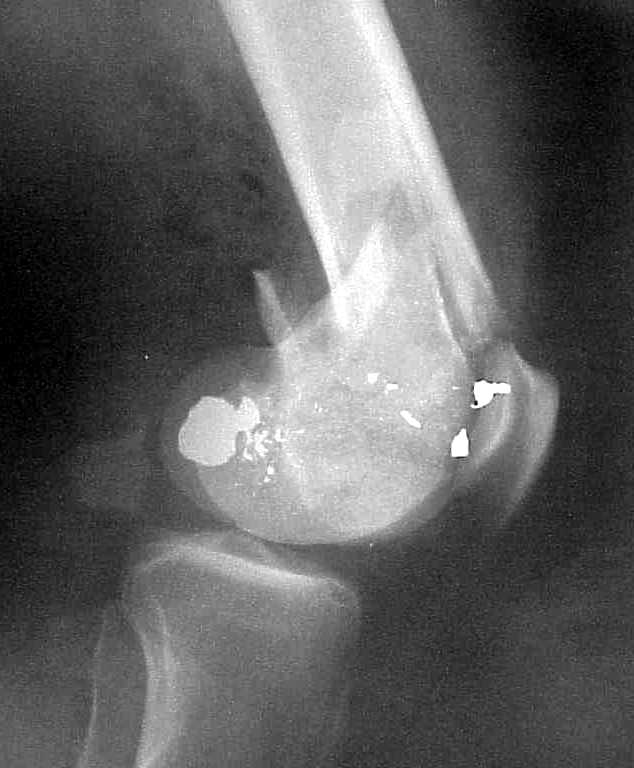

Use 6.5 mm cannulated screws if you have and

place one anterior to where IMN will go if anterior cortex if insufficient and AP screws on either side of the IMN out of the trochlea to provide some additional varus/valgus stability. I worry about the leg going into valgus w/the lack of lateral cortex.

See attached case that was done several years ago before LISS. He had comminuted trochlea and anterior blocking screws were used to prevent anterior IMN cut-out.